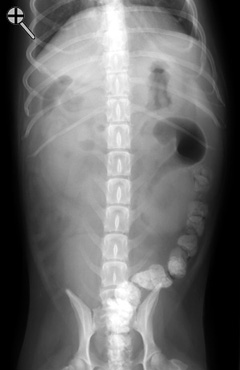

Survey radiographs are taken before administering barium. If you have any questions concerning the technique of an upper GI series, click here to review. Do you notice anything incorrect about the preparation of this patient? YES or NO .